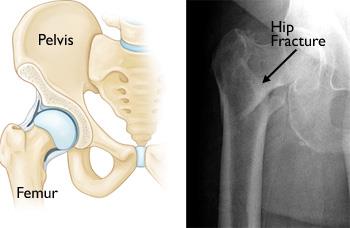

Recovery Hip fractures are cracks or breaks in the top of the thigh bone femur close to the hip joint. For many a hip fracture means a long stay in the hospital followed by recovery in an assisted care facility. For a few a hip fracture will mean the permanent loss of mobility and independence.

Not all symptoms associated with hip fracture will be present for this condition to be confirmed. Theyre usually caused by a fall or an injury to the side of the hip but may occasionally be caused by a health condition such as cancer that weakens the hip bone. Try to stay at your ideal weight.